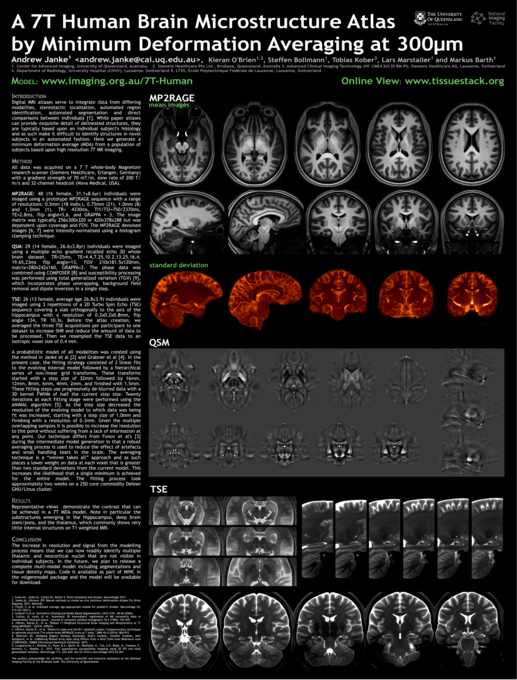

Digital MRI atlases serve to integrate data from differing modalities, stereotactic localisation, automated region identification, automated segmentation and direct comparisons between individuals [1]. While paper atlases can provide exquisite detail of delineated structures, they are typically based upon an individual subject's histology and as such make it difficult to identify structures in novel subjects in an automated fashion. Below are a number of atlases generated via minimum deformation average (MDA) from a population of subjects based upon high resolution 7T MR imaging.

All data was acquired on a 7 T whole-body Magnetom research scanner (Siemens Healthcare, Erlangen, Germany) with a gradient strength of 70 mT/m, slew rate of 200 T/m/s and 32-channel headcoil (Nova Medical, USA).

A probabilistic model of all modalities was created using the method in Janke et al [2] and Grabner et al [4]. In the present case, the fitting strategy consisted of 2 linear fits to the evolving internal model followed by a hierarchical series of non-linear grid transforms. These transforms started with a step size of 32mm followed by 16mm, 12mm, 8mm, 6mm, 4mm, 2mm, and finished with 1.5mm. These fitting steps use progressively de-blurred data with a 3D kernel FWHM of half the current step size. Twenty iterations at each fitting stage were performed using the ANIMAL algorithm [5]. As the step size decreased the resolution of the evolving model to which data was being fit was increased, starting with a step size of 1.0mm and finishing with a resolution of 0.3mm. Given the multiple overlapping samples it is possible to increase the resolution to this point without suffering from a lack of information at any point. Our technique differs from Fonov et al's [3] during the intermediate model generation in that a robust averaging process is used to reduce the effect of artefacts and small handling tears in the brain. The averaging technique is a “winner takes all” approach and as such places a lower weight on data at each voxel that is greater than two standard deviations from the current model. This increases the likelihood that a single minimum is achieved for the entire model.

The increase in resolution and signal from the modelling process means that we can now readily identify multiple thalamic and neocortical nuclei that are not visible in individual subjects. In the future, we plan to release a complete multi-modal model including segmentations and tissue density maps. Code is available as part of MINC in the volgenmodel package

MP2RAGE - MP2RAGE T1 style model

GRE/QSM - Model generated from QSM data

TSE - Turbo Spin Echo Hippocampal model